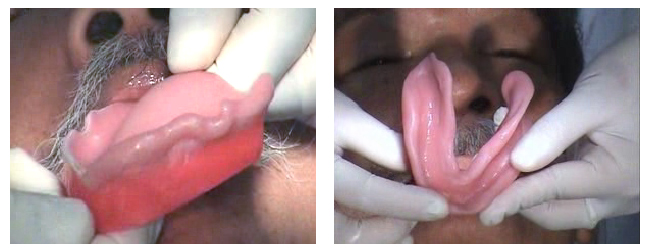

ภาพแสดงการลอง

occlusion rim และการตรวจสอบ